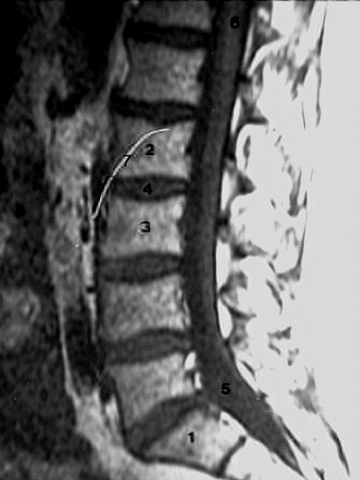

Back- Lumbar Spine MRI zoom

1. First sacral vertebra

2. Body of the 2nd lumbar vertebra

3. Body of the 3rd lumbar vertebra

4. Intervertebral disc

5. Lumbar cistern

6. Spinal cord

7. Artifact.